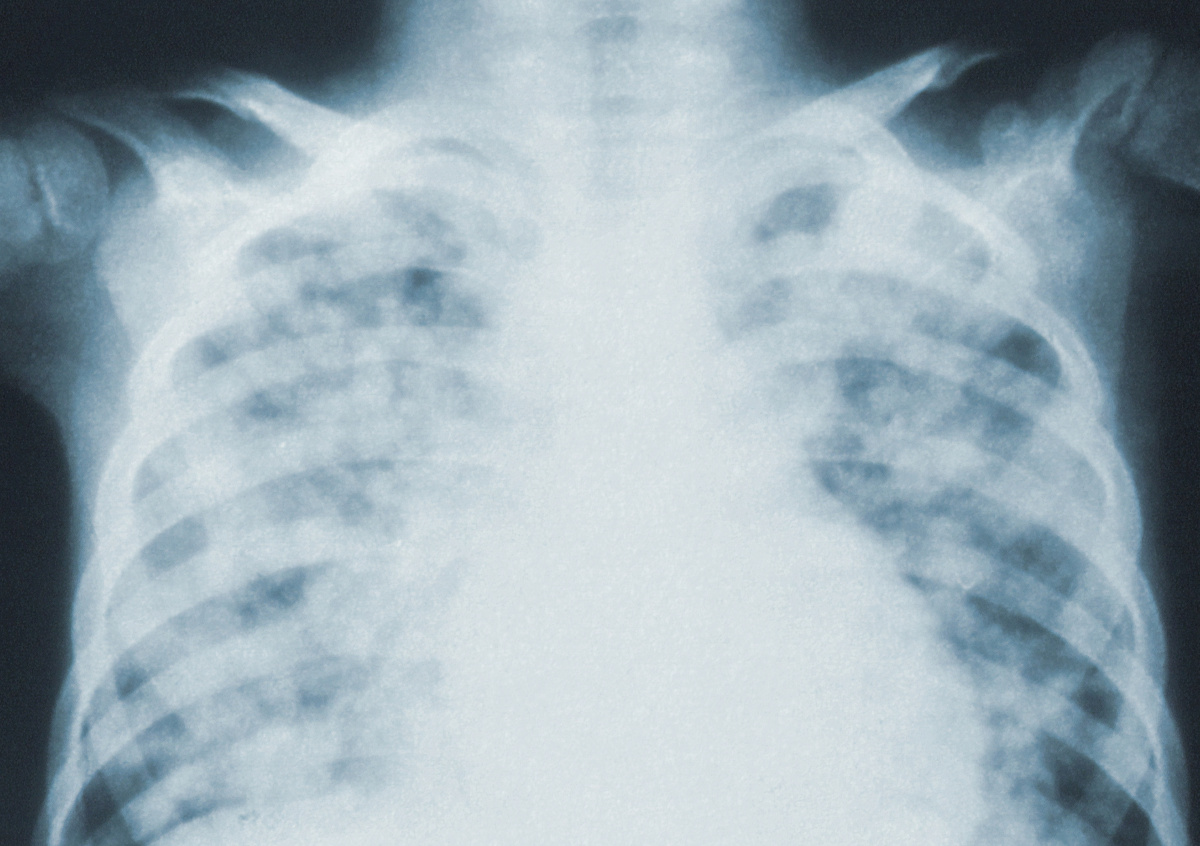

Врачи нашли рак лёгких четвёртой стадии у некурящей беременной австралийки

Бладуэлл ни разу в жизни не курила и не могла представить, что столкнётся с онкологическим заболеванием такого рода, пишет Daily Mirror. Биопсия и компьютерная томография показали, что опухоль дала метастазы, которые распространились на оба лёгких, спину и мозг.